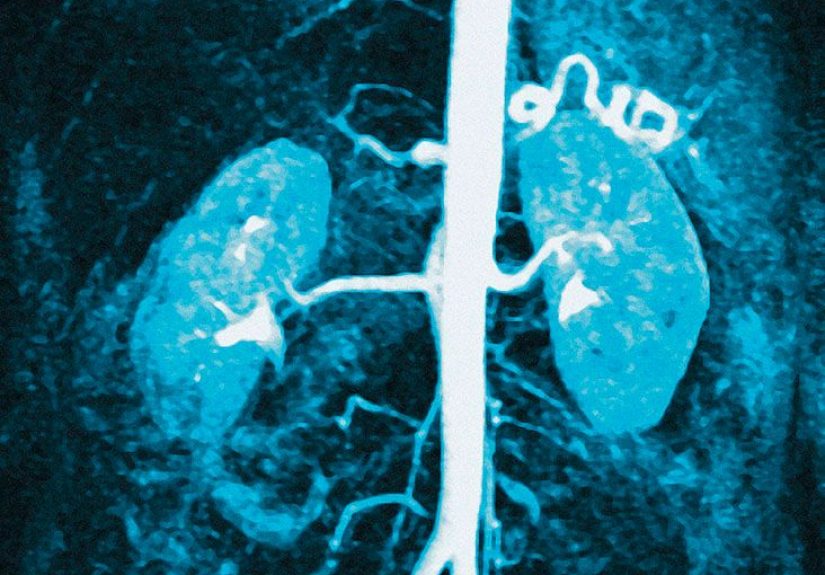

Diabetic nephropathy is kidney damage caused by diabetes. Over time, high blood sugar injures the tiny filtering units in the kidneys. At first, this damage is quiet. There may be no obvious symptoms at all. That silence is one reason diabetic kidney disease can creep forward for years before someone realizes it is happening.

Healthy kidneys filter the blood and help the body get rid of extra potassium through urine. When diabetic kidney disease lowers kidney function, that potassium removal system becomes less efficient. The result can be a gradual rise in blood potassium, especially as chronic kidney disease gets more advanced.